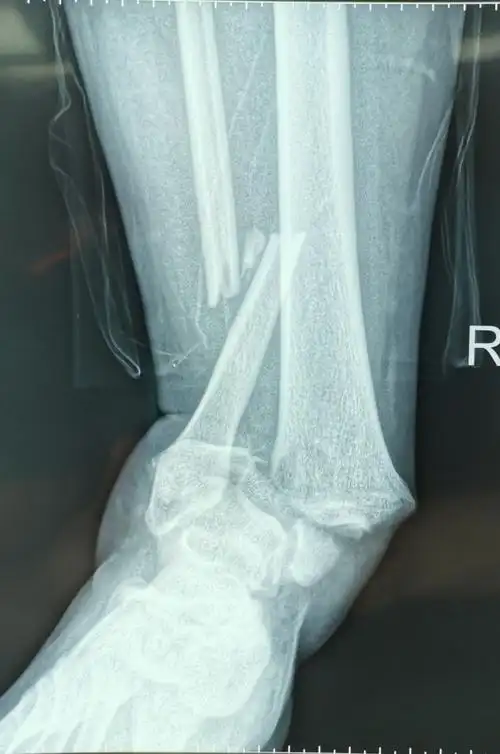

特殊类型踝关节骨折:logsplitter损伤